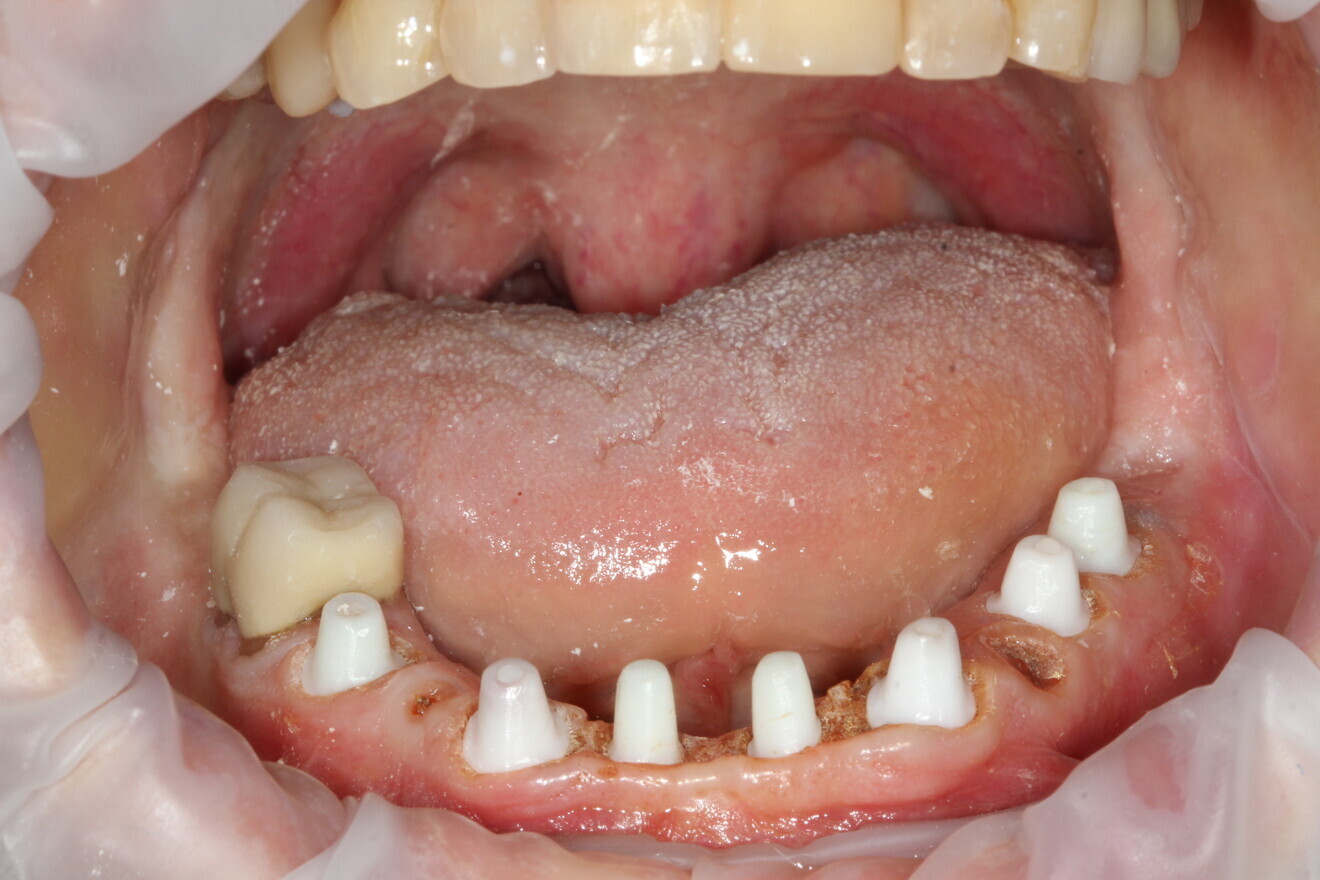

Fig. 1: Failing mandibular dentition. (All images: Daniel Madden)

The patient presented with multiple periapical radiolucencies associated with failing endodontically treated teeth, a horizontal root fracture and a failing long-span bridge (Fig. 1). A poor long-term prognosis was given to all the remaining mandibular teeth except tooth #46 (Fig. 2), and the treatment options, limitations and risks were reviewed thoroughly with the patient. The patient did not want a removable restoration and did not want to go a day without teeth and wanted to have biologically friendly materials used for treatment. It was decided to perform an immediate implant surgery and provide the patient with a stable temporary restoration to protect the healing implants for long-term success.